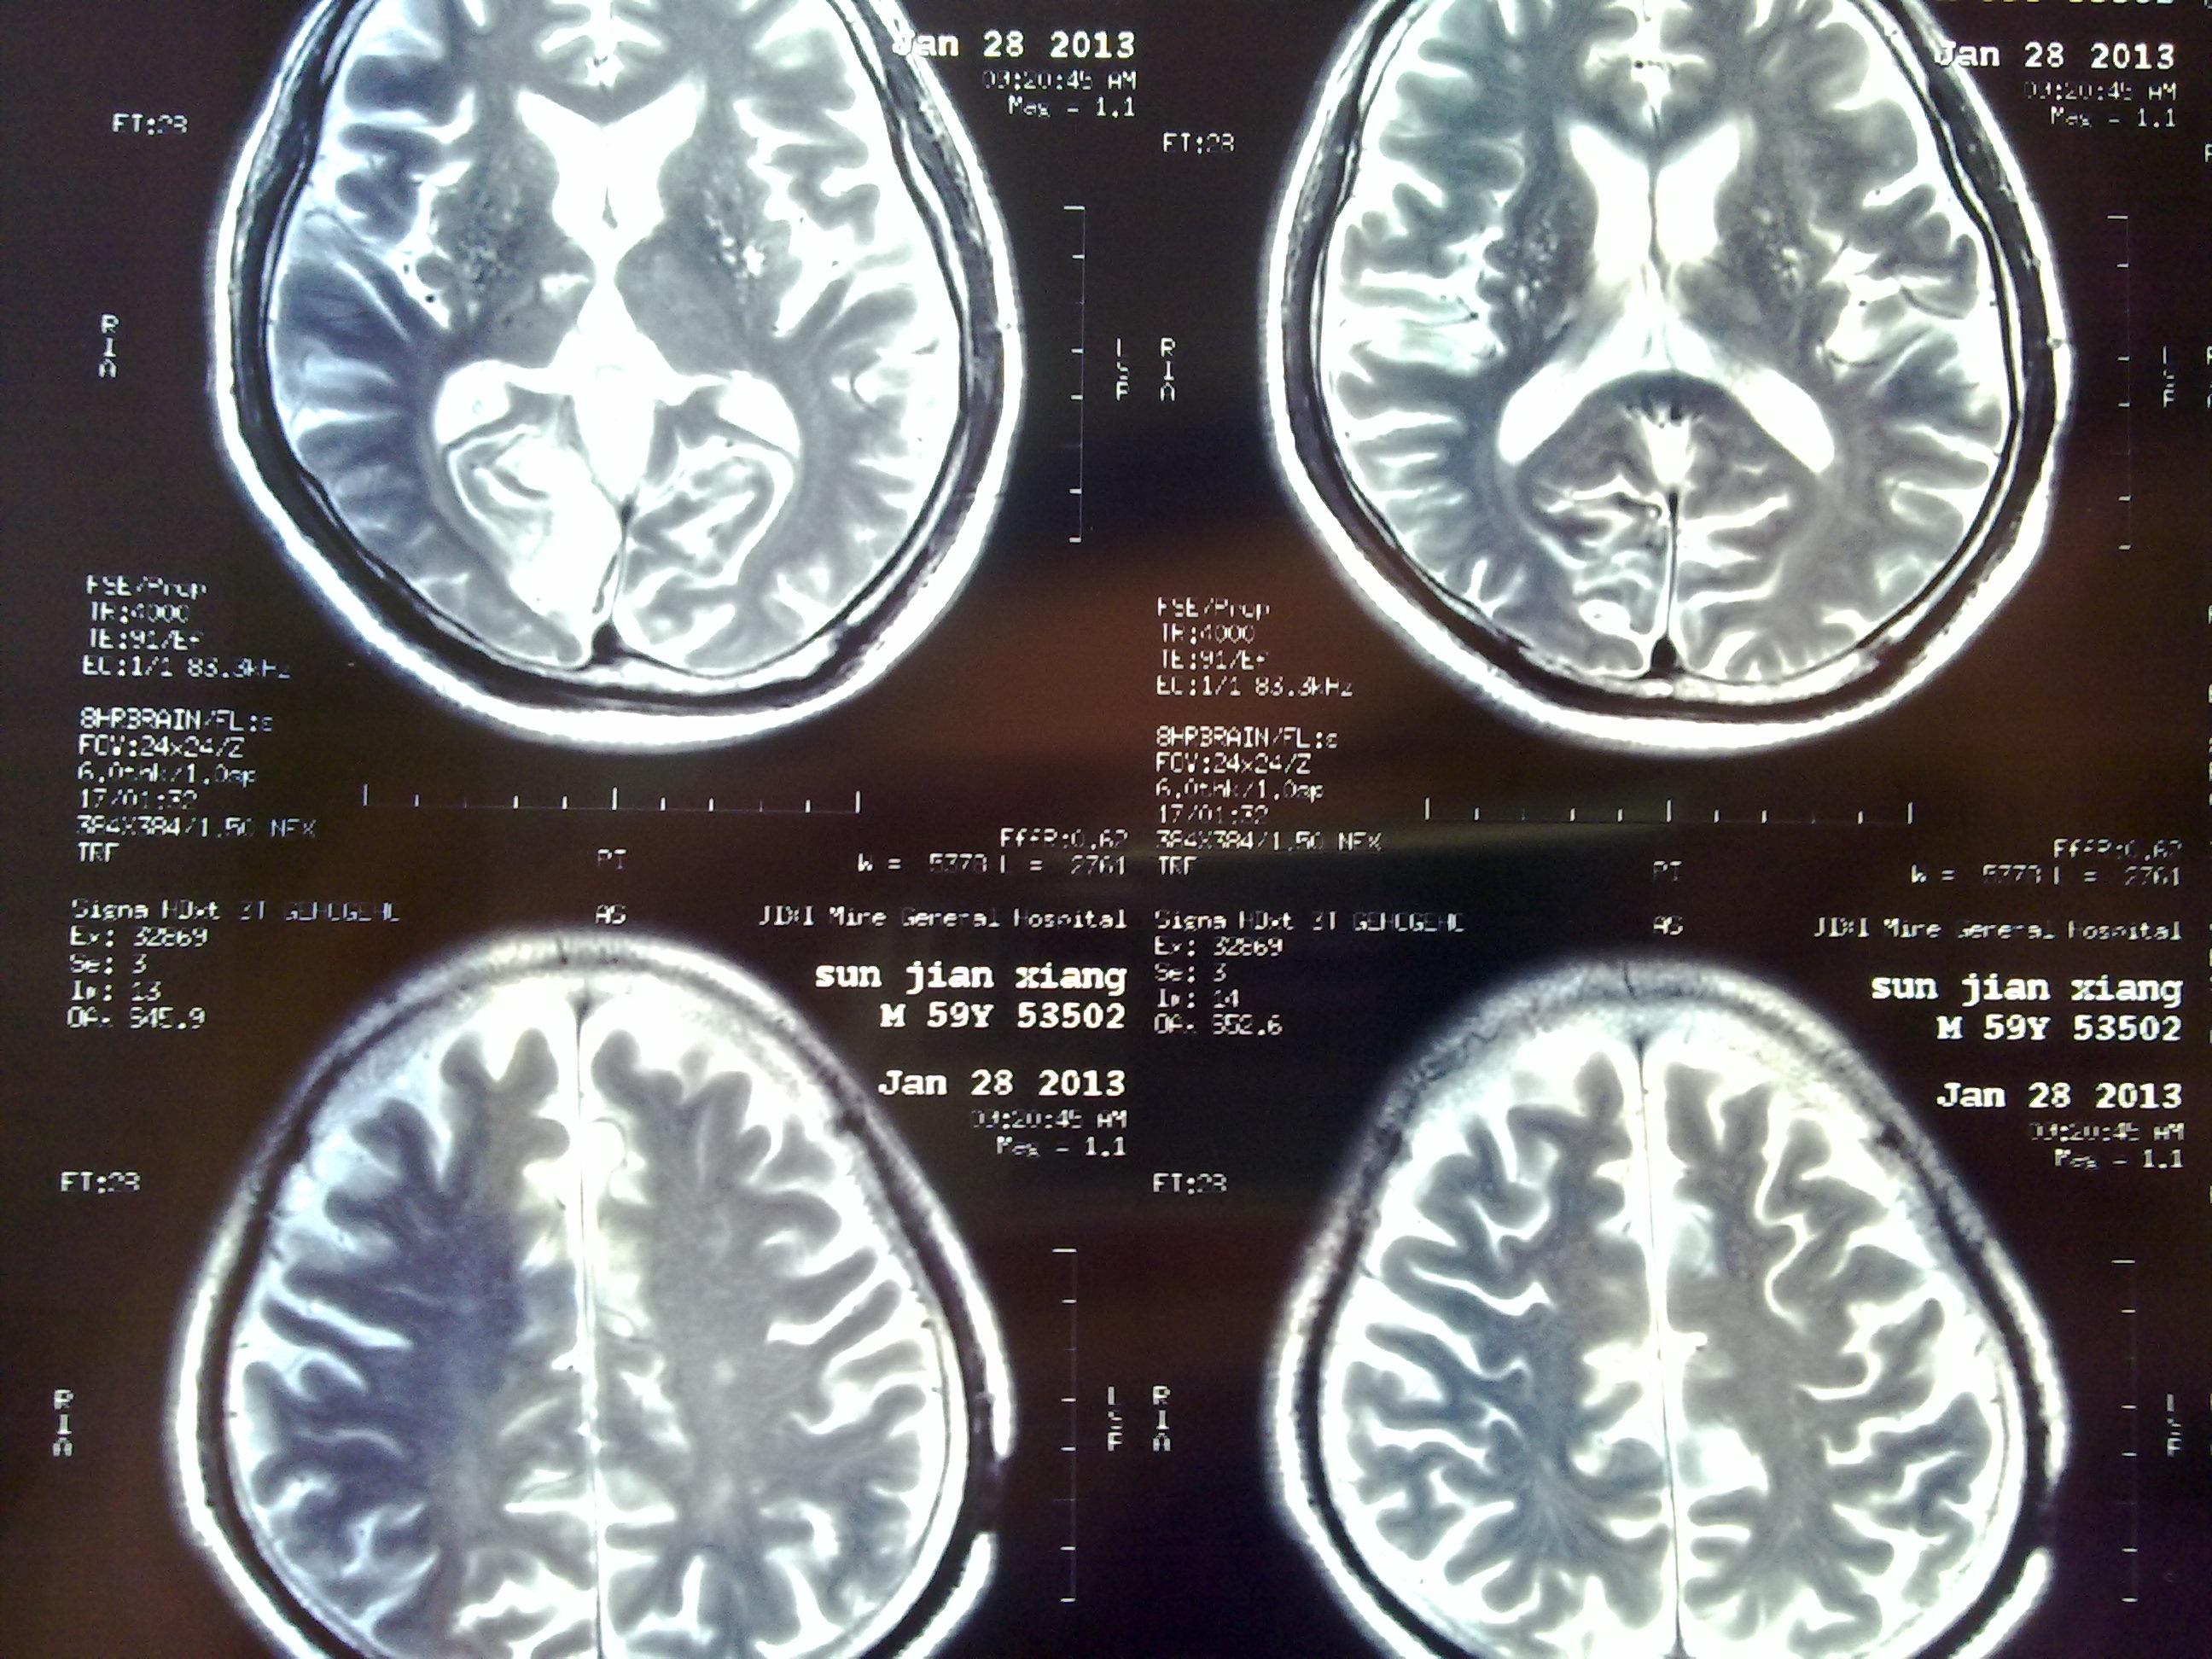

脑梗塞病人的头ct片,大家看看下一步的治疗

图片尺寸2592x1944